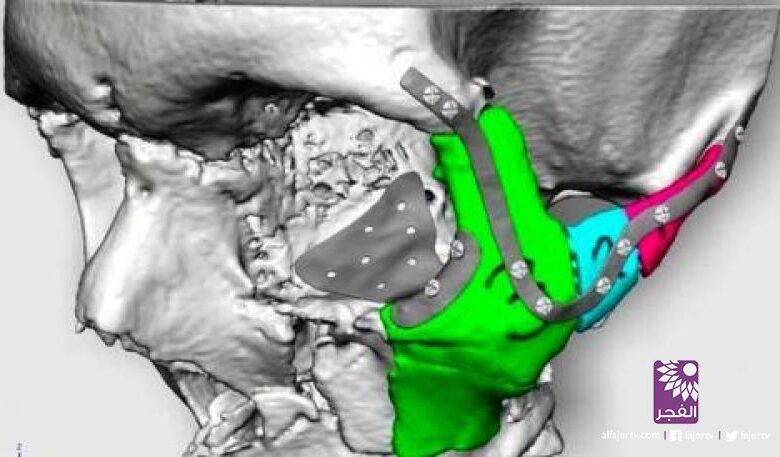

وباستخدام أبعاد الجهة غير المتضررة من وجه الرجل، أخذ الجراحون صورة عكسية لها، لتصميم الجهة المتضررة من وجهه لترميمها.

واستخدم الجراحون تقنية العالم الافتراضي لوضع التصميم النهائي للعظام المتحطمة من وجه الرجل، وهي عبارة عن 3 عظام من أجل زراعتها.

واعتمد الأطباء على طباعة عظام بديلة من مادة التيتانيوم الطبية، تمت طباعتها في بلجيكا، حيث توجد واحدة من عدد محدود من مرافق الطباعة الثلاثية الأبعاد المتخصصة في العالم.

واستخدم الأطباء في مدينة سوانزي جنوبي ويلز في بريطانية التصوير المقطعي المعتمد على الكمبيوتر للحصول على صور ثلاثية الأبعاد بالغة الدقة لتصميم عظام وجه الرجل.